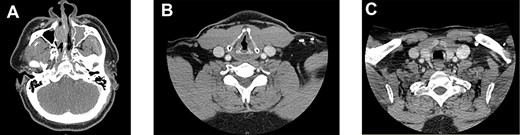

The patient had CT head and neck with contrast enhancement after the initial procedure (Fig. 2A–C).

Imaging. (A) Complete opacification of the left maxillary sinus. There is also destruction of the nasal septum, which is consistent with post-operative changes. (B) A 2 mm nodular thickening of the left vocal cord. (C) A 2 mm thickening of the anterior trachea, consistent with intraoperative findings in the first procedure. This lesion was treated with debridement and Cidofovir in the second procedure.